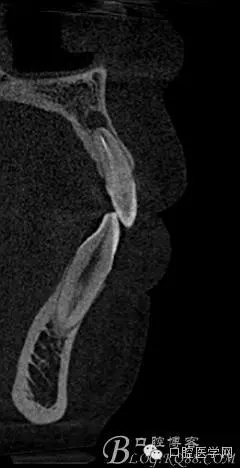

檢查前拍全景發(fā)現(xiàn)問題

根尖區(qū)低密度影像+根管欠充填

補(bǔ)拍CBCT進(jìn)行診斷分析

CBCT測量得出根尖囊腫3×4mm,進(jìn)行常規(guī)根管充填后行根尖切除術(shù)